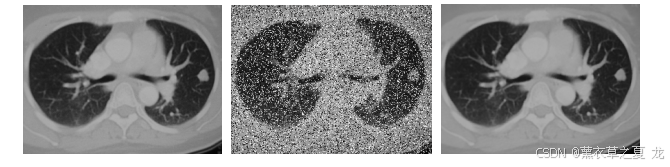

实验2 在原始图像添加方差0.25的椒盐噪声, 采用7X7的滤波窗口处理图像。图2为处理后的图像,表2为对应的RPSN值。

图2(a)原始图像 图2(b)添加方差0.25椒盐噪声 图2(c)滤波后图像

图2

结合比较图1和图2,表1和表2可得:实验2中添加了方差为0.25的椒盐噪声模糊的图像的大部分细节,但中值滤波都取得了不错的去噪效果,基本上去除了噪声的影响。对比采用3X3和7X7窗口的中值滤波效果,同时结合对应的RPSN值,可以看出采用7X7窗口的中值滤波,边缘细节有不少损失,图像比采用3X3窗口的方法更加模糊。可得结论为:中值滤波对于低密度的噪声信号有很好的去噪效果,但对于高密度的噪声去噪效果不是非常好。